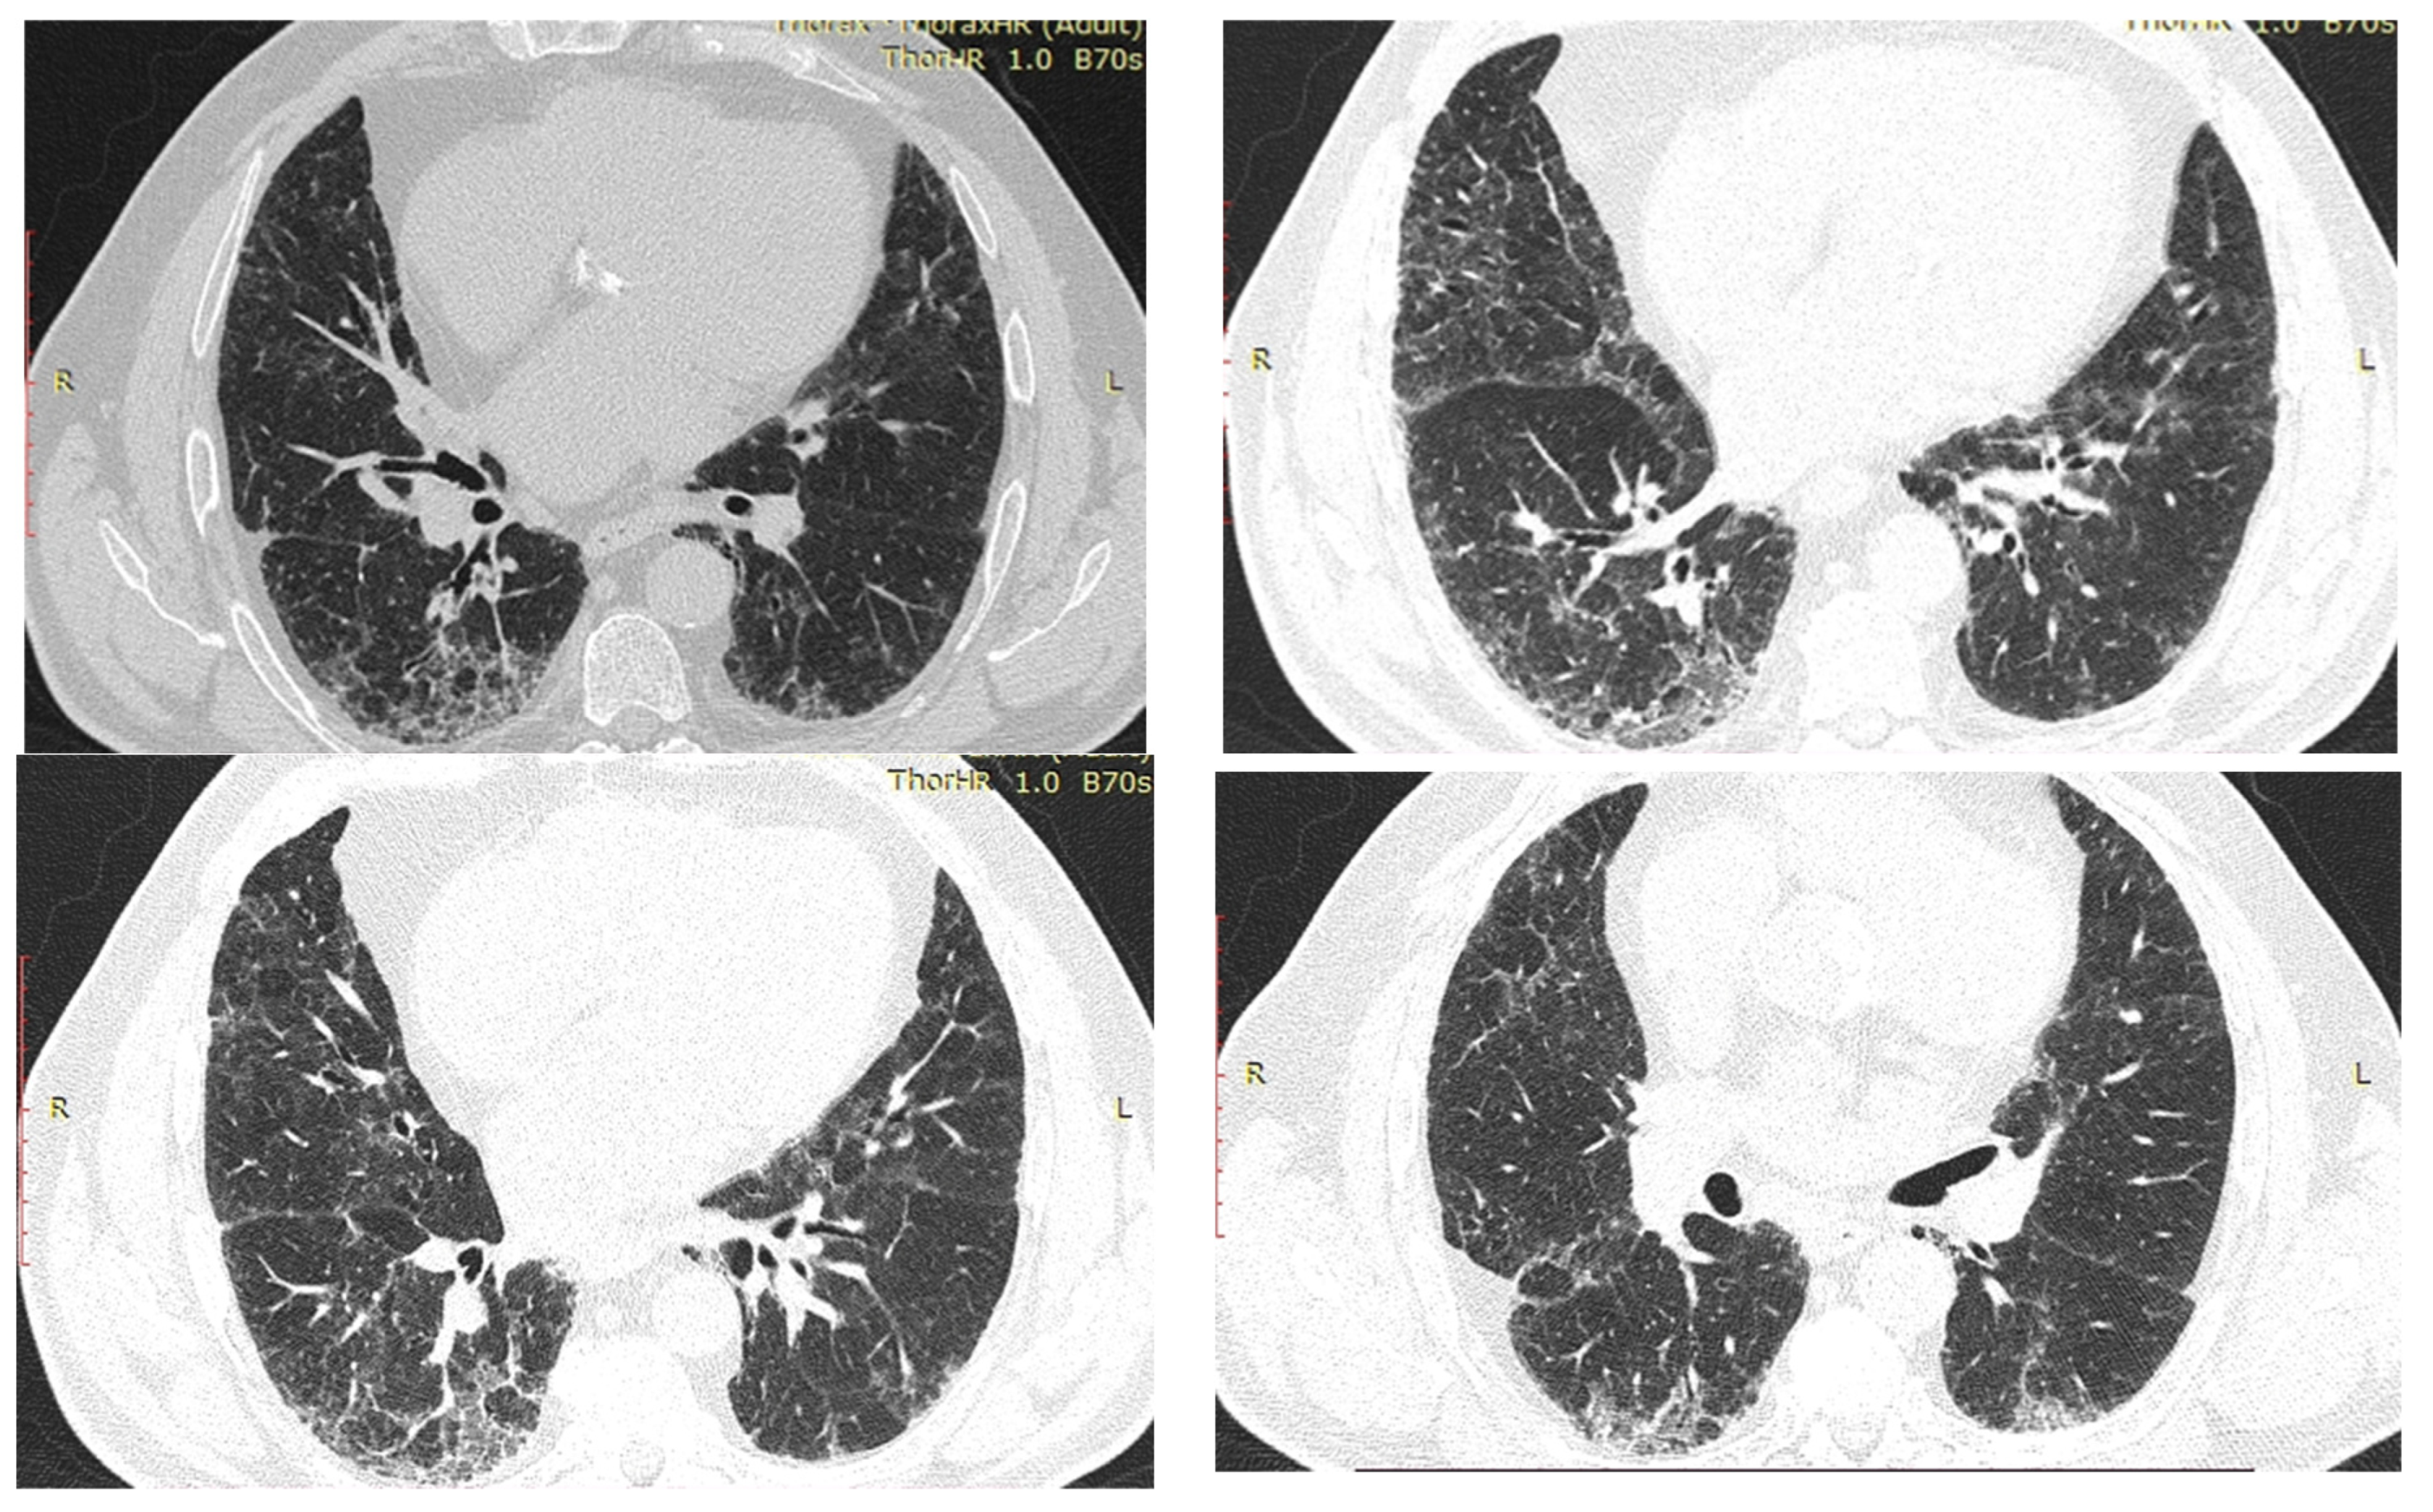

2.3. Case Presentation 3